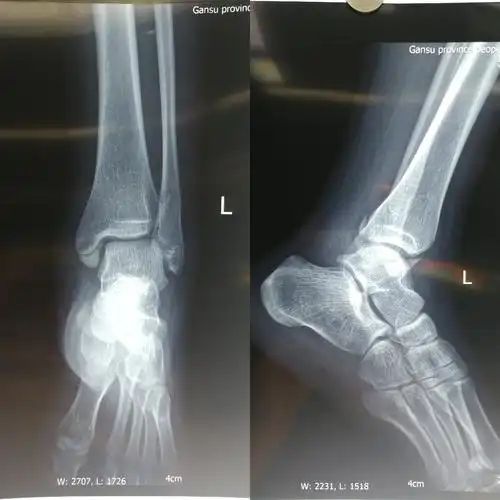

术前x线正侧位